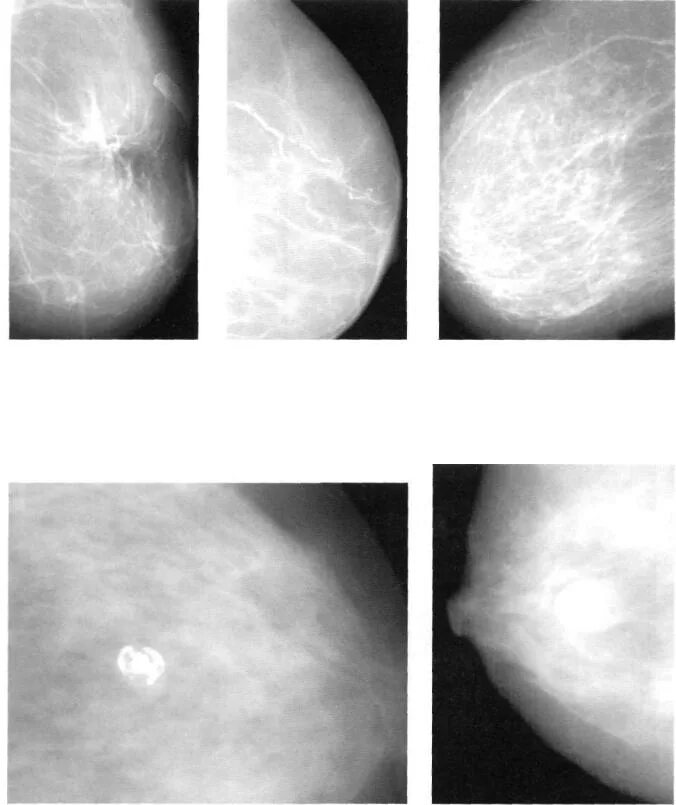

Формы уплотнений в молочной железе